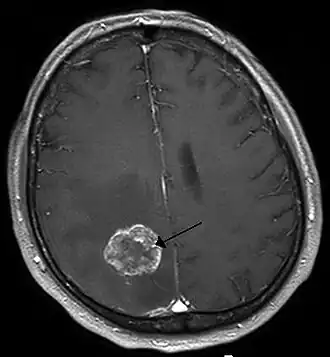

Afbeelding van een MRI-scan van een uitzaaiing van longkanker in de rechterhersenhelft (L=links, P=occipitaal, achterkant van het hoofd). | ||||